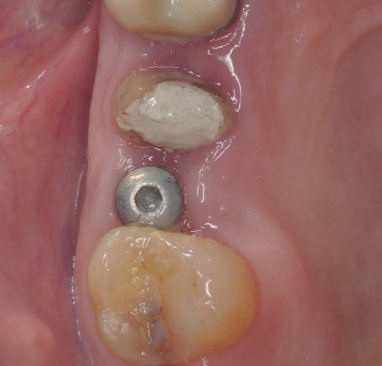

En la Historia Clínica no se evidenciaron antecedentes médico-quirúrgicos de interés, alergias medicamentosas conocidas ni hábitos nocivos. En la exploración intraoral, se apreció un implante en la localización del 1.6, con un pilar de cicatrización, y el diente 1.5 con un ferrule insuficiente para ser restaurado (Figura 1). En la exploración radiográfica, mediante escáner de haz cónico (CBCT), se apreció un tratamiento de conductos en el 1.5, así como una imagen radiolúcida a nivel apical (Figura 2). Se planificó la exodoncia del 1.5, para lo que se firmó previamente el consentimiento informado. Tras el mismo, se realizó un bloqueo anestésico mediante articaína al 4% con adrenalina 1:100.000 del nervio alveolar superior posterior y medio y el nervio palatino anterior. Se realizó la extracción de la forma más atraumática posible y se eliminaron del diente el cálculo y los restos de obturaciones con fresa de diamante de turbina (Dentsply Maillefer, Ballaigues, Suiza). Se pulió la superficie radicular con fresas de diamante de turbina con abundante irrigación, eliminando de esta forma el ligamento periodontal. El material de relleno endodóntico fue retirado usando fresas de Gates Glidden® (Dentsply Sirona Inc, Delaware, Estados Unidos) (Figura 3). Se cortó el diente en fragmentos ≤ 5 mm y se colocaron secos dentro del molino del dispositivo Tooth Transformer® (S.R.L, Milan, Italia) como indica el fabricante.

Cinco meses tras la colocación del implante, se realizó la toma de impresiones para la realización de una corona cemento-atornillada sobre una base de titanio. Un año tras la colocación de la corona, se observó el buen aspecto gingival (Figura 14) y radiográfico, donde se observa una pérdida ósea marginal fisiológica en las radiografías periapicales (Figura 15), y en los cortes del CBCT (Figura 16).